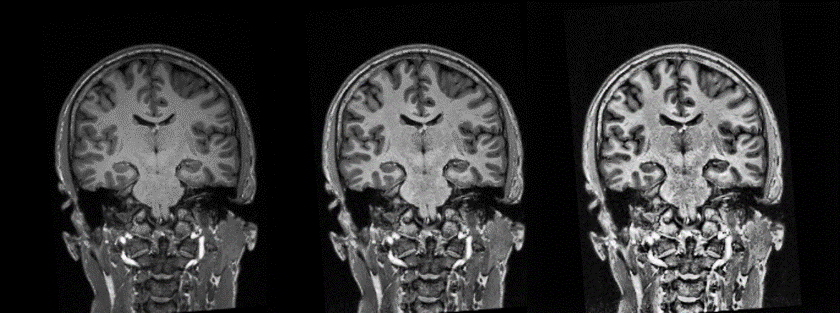

Figure 1 Original image (left). AHE processed with Window

size= 30 and Clipfactor = 300 (centre) and with Clipfactor=100 (right)